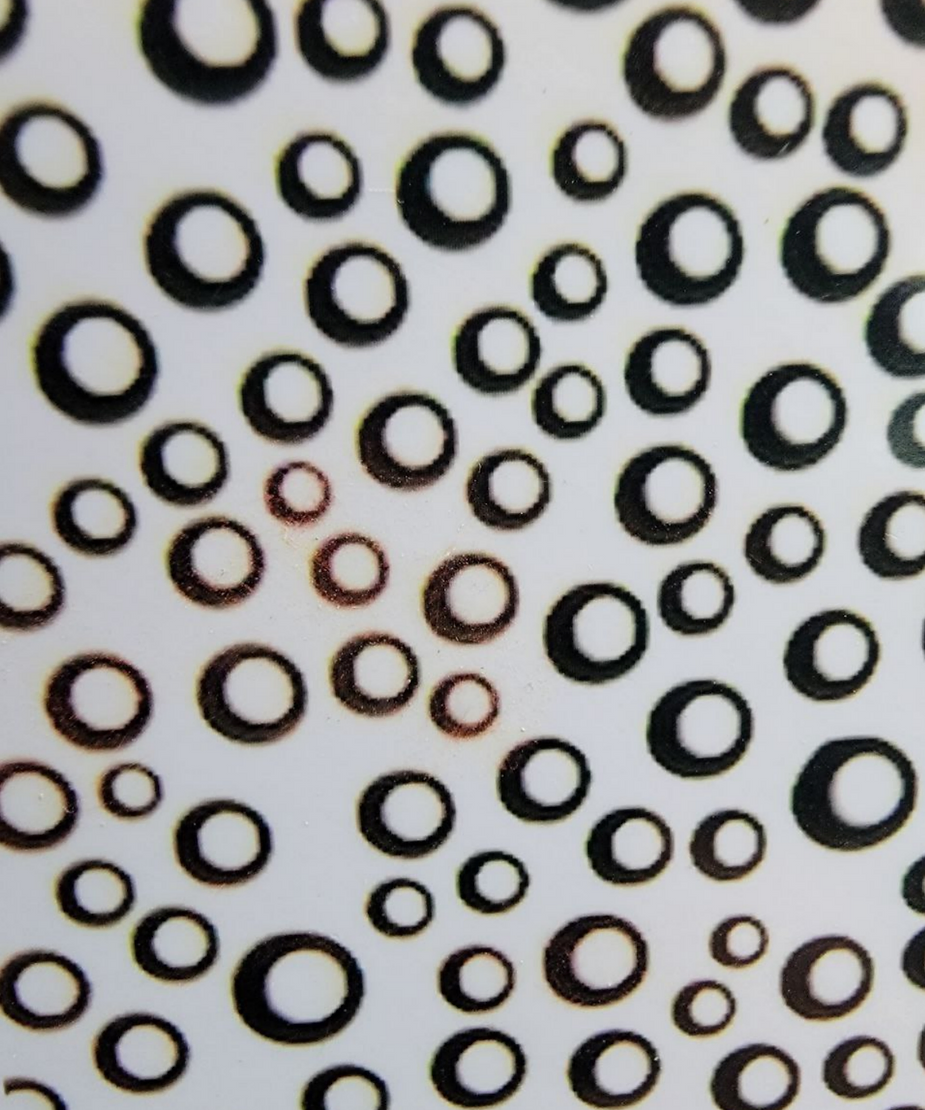

In an article from The Expose entitled: Covid Injection Aftermath: Study finds 94% of “Vaccine” Recipients have Pre-Blood Clot Formations and Foreign Particles, by Rhonda Wilson, on 8/24/2022 the author states: An Italian study published two weeks ago in the International Journal of Vaccine Theory, Practice, and Research revealed almost everyone who had been injected had abnormalities after Covid vaXXXination. In 94% of vaXXXinated blood, there was an aggregation of red blood cells and the presence of particles of various shapes and sizes. The study began in March 2021. Using dark-field microscopy, the researchers analyzed blood samples from 1,006 referred to the Giovannini Biodiagnostic Centre for various disorders after being injected with Pfizer/BioNTech or Moderna mRNA vaccines.

In the study, authors noted that the vaccines are purported to contain at least the spike protein from SARS-CoV-2 but are known also to contain foreign particles. “Among those foreign components are metallic objects as demonstrated previously in this journal by Lee et al. (2022) which are confirmed in our results.” Of the 1,006 cases analyzed, only 58 – equal to 5.77% of the total – presented a completely normal hematological picture upon microscopic analysis after the last mRNA injection with either the Moderna or Pfizer vaccine. The blood of 948 – 94% of the study’s participants – showed aggregation of red blood cells and the presence of particles of various shapes and sizes of unclear origin one month after the mRNA injection.